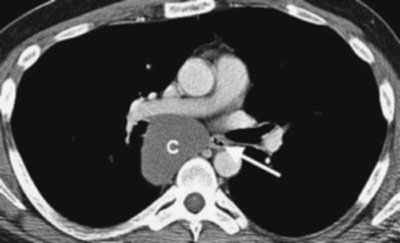

An intrathoracic thyroid mass is usually a benign multi-nodular goiter that originates in the neck and extends downward into the mediastinum through the thoracic inlet. This continuity is an important diagnostic feature on chest radiography. Many thyroid masses displace or narrow the trachea (Fig. 6-7). Another useful sign of a thyroid mass is the relative high attenuation value of the thyroid tissue, at least 20 Hounsfield units above that seen in adjacent muscles on both precontrast and postcontrast computed tomographic (CT) images (2). CT scans can show cystic components. Calcification is common and usually caused by benign disease when it is dense, amorphous, and well defined with a nodular, curvilinear, or circular configuration. Distinguishing between benign and malignant thyroid masses on chest radiography or CT scanning is not possible unless the tumor has clearly spread beyond the

thyroid gland (indicating malignancy). Malignant thyroid masses can also have calcifications, generally with a configuration of fine dots grouped in a cloudlike formation (3,4,5). However, the patterns of benign and malignant calcifications serve as general guidelines, and malignant medullary thyroid carcinoma can contain well-defined, occasionally ring-shaped, dense calcifications that are similar in appearance to the calcifications seen with benign thyroid goiter. Radionuclide imaging is a very sensitive and specific method of determining the thyroid nature of an intrathoracic mass (Fig. 6-8), but CT provides more information about the mass.